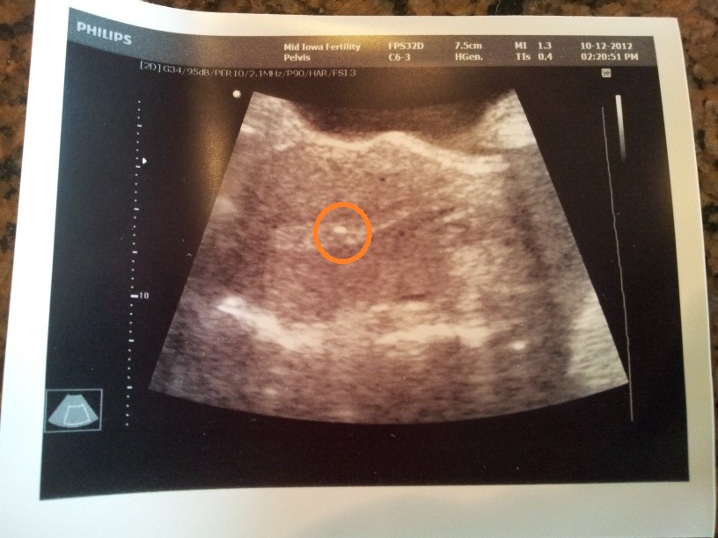

WP_006236 October 12, 2012 by Courtney Leave a comment ← Previous Image Embryos transferred to my uterus, where they belong!